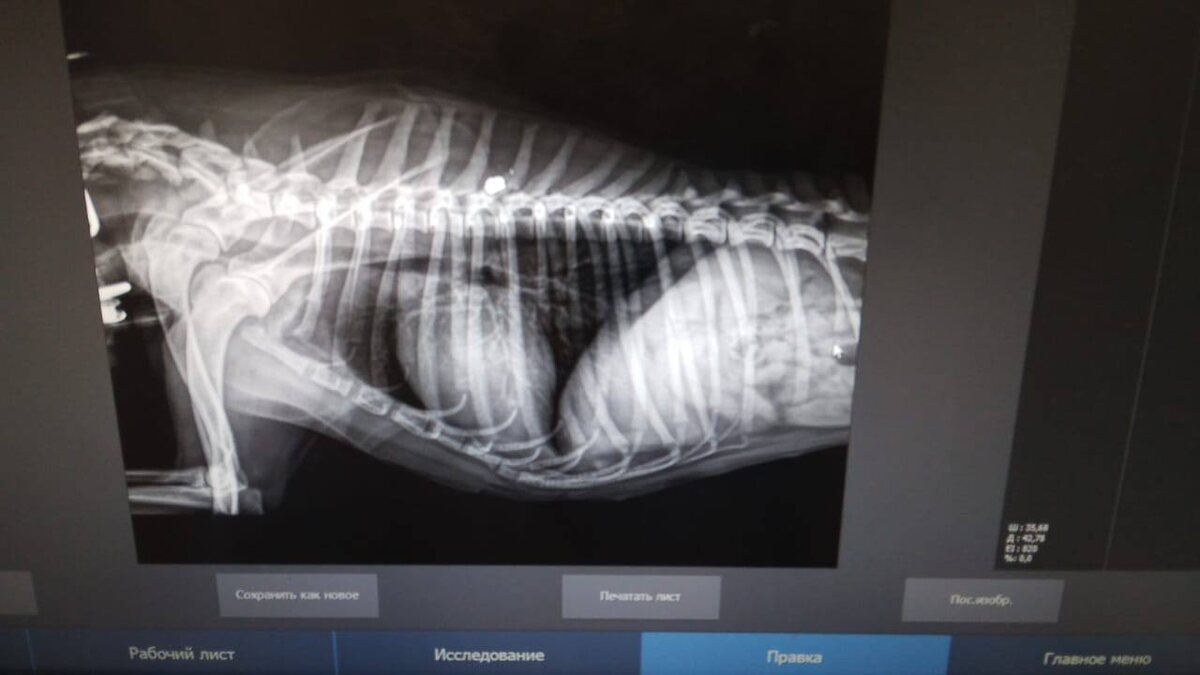

Пулевое ранение в грудь, травма позвоночника. Опять отстрел собак. Что, опять, наверное, маленькая собачка чьей-то жизни угрожала????

Ей ОЧЕНЬ нужен стационар, обследование , операции на позвоночнике.